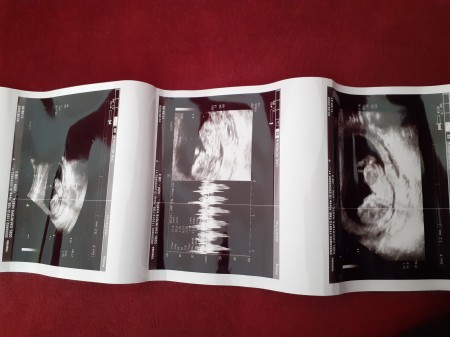

12 haftaligim ve dün doktor %90 erkek dedi acaba daha değişir mi?

12 haftaligim ve dün doktor %90 erkek dedi acaba daha değişirmi ki

Canım ultrason resmini atar mısın

anlayan varmi

Atmasın görmemiştim evt cnaim çıkıntı var erkek

Ve aynı benim 12+4 deki usg erkek ti

Usg atarmışım cnaim bakiyim tahmin yapıyorum net pipi yi gördü ise evt erkek tir değişmez